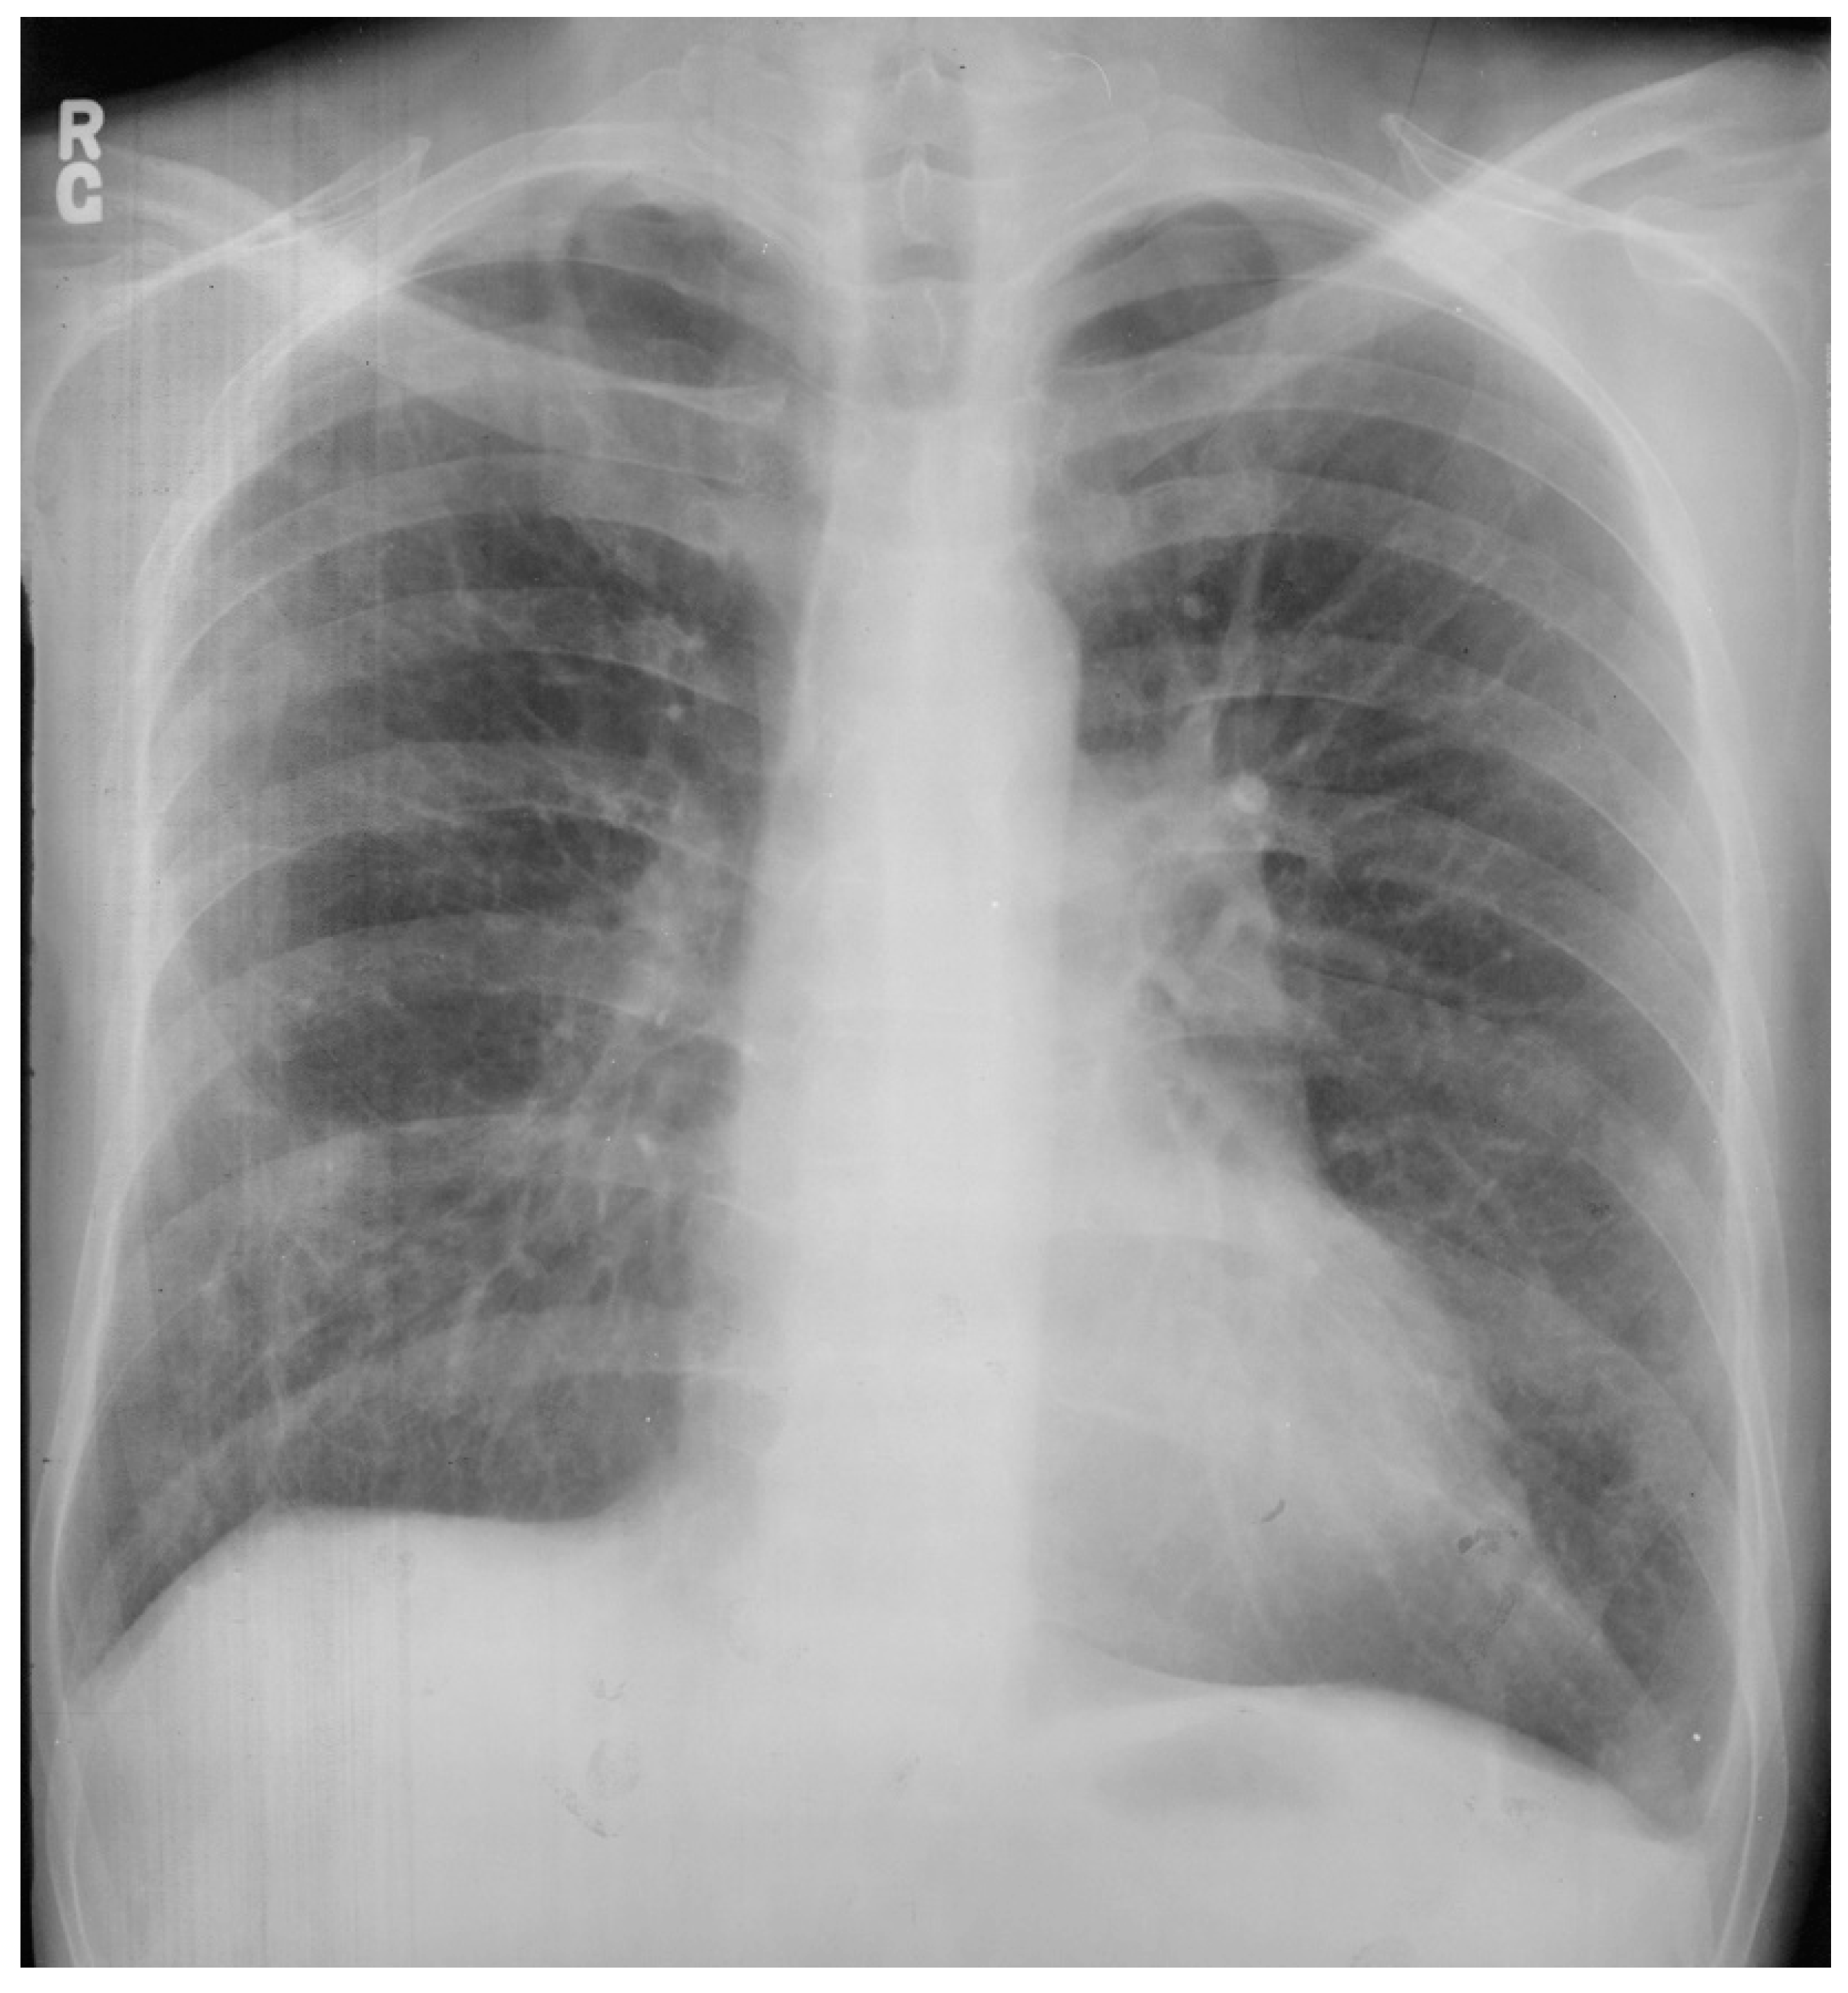

An atrial septal defect (ASD) is among the most common congenital heart defects. A persistent ASD in the region of the fossa ovalis is called ostium secundum atrial septal defect (OSASD) and it comprises 75% of all ASDs. An OSASD (Figure 8) is different from a Patent Foramen Ovale (PFO), which is an interatrial communication in which the septum primum covering the fossa ovalis overlaps the superior limbic band of the septum secundum [10]. A PFO is usually closed when the pressure in the left atrium exceeds the pressure in the right atrium, but it opens when right atrial pressure exceeds left atrial pressure. A native OSASD results in left-to-right shunting across the defect, right ventricular volume overload and pulmonary overcirculation. A large left-to-right shunt may result in flow-related pulmonary artery hypertension and pulmonary vascular obstructive disease may develop in adult years [10]. The initial adult presentation of OSASD is most often characterized by symptoms of dyspnea and palpitations. Physical examination includes a precordial lift, a systolic pulmonary flow murmur and, usually, fixed splitting of S2. The PA CXR may show right atrial enlargement, a prominent pulmonary artery segment and increased pulmonary vascularity (Figure 10). In the presence of pulmonary vascular obstructive disease the CXR will demonstrate pruning of peripheral pulmonary arteries.

Figure 10.

Posteroanterior chest X-ray of ostium secundum atrial septal defect (OSASD): This is a chest X-ray of a 46-year-old male with an uncorrected OSASD. The image is slightly rotated. There is a good inspiration. The cardiothoracic ratio is increased. The pulmonary trunk is enlarged and there is a lateral rim of calcification. Compared to the enlarged central pulmonary circulation the more peripheral pulmonary vessels are much smaller (called pruning), suggesting pulmonary vascular obstructive disease. The lower right heart border demonstrates right atrial enlargement. The aortic knob is smaller than the pulmonary trunk, indicating a significant left to right shunt.